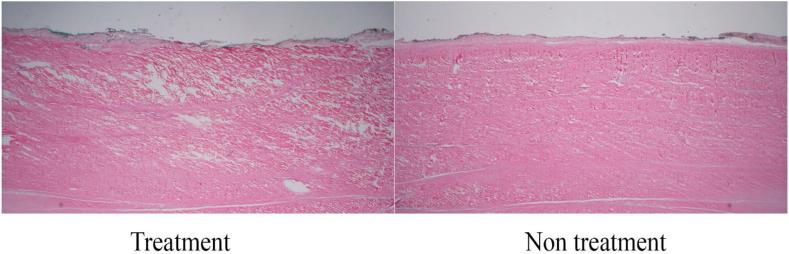

Twelve bovine soleus tendons were allocated to four cohorts to undergo PUTT for 1, 3, 5, and 7 min. Each specimen was treated on one side, the opposite side serving as a control. Macroscopic and microscopic analyses were conducted to assess tendon sheath, fascicle, and perineural disruption. Fascicle penetration was measured using ImageJ software. Statistical analyses were performed using Analysis of Variance (ANOVA), with significance levels set at p < 0.05.

Macroscopic and microscopic examination revealed progressive separation of the paratenon, peritendinous nerves, and fascicles, correlating with increased treatment duration. Fascicle penetration depths were 0.1 mm, 2.57 mm, 2.61 mm, and 3.93 mm at 1, 3, 5, and 7 min, respectively. ANOVA confirmed significant differences among groups (F (3, 8) = 620.898, p < 0.001), with a large effect size (η = 0.996. Tukey's Honest Significant Difference (HSD) test revealed significant differences between most groups (p < 0.001), except between the 3-min and 5-min treatments, which showed no significant difference (p = 0.969).

PUTT induces significant structural changes in the paratenon and fascicle layer with longer treatment duration, resulting in more pronounced modifications.